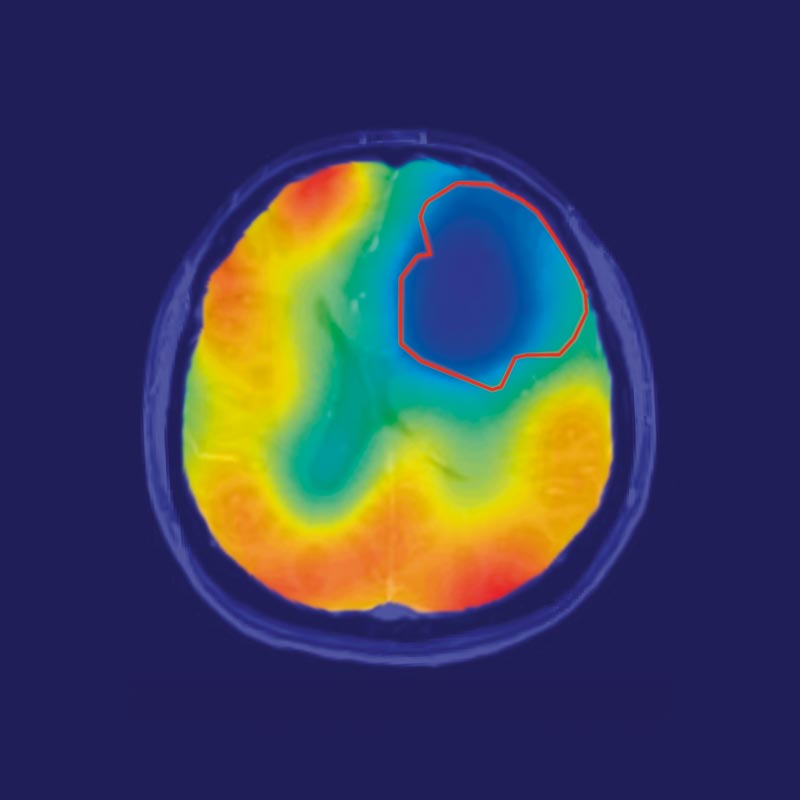

Bösartige Hirntumoren: Optimierung der Diagnostik durch moderne Bildgebungsverfahren

Die Diagnostik von Hirntumoren beruht heute in erster Linie auf der Magnetresonanztomographie (MRT). Die MRT ist weit verfügbar und bietet eine hervorragende…